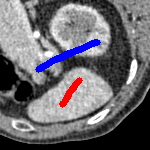

The motivation for this work comes from observing contradictions in using piecewise-constant intensity fitting terms in selective segmentation. Whilst good results are possible with this approach, the exceptional cases lead to severe limitations in practice. This is quite common in medical imaging as demonstrated in Fig. 1, where the target foreground has a low intensity. Given that the corresponding background includes large regions of low intensity, the optimal average intensities for this segmentation problem are and . For cases where , we see that by (1), almost everywhere in the domain . This means that it is very difficult to achieve an adequate result, without an over-reliance on the user input or parameter selection.

for and as defined in (33). This is consistent with respect to the intensities of the observed object and the concept of selective segmentation. In Fig. 3 we see the difference between CV and the proposed fitting terms for given user input on a CT image. For the CT image, the CV fitting terms are near 0 within the target region. This is despite there being a distinct homogeneous area with good contrast on the boundary. This illustrates the problem we are aiming to overcome. With the proposed fitting term this phenomenon should be avoided in cases like this. By defining as in (33) there is no contradiction if the foreground and background intensities of the target region are similar.